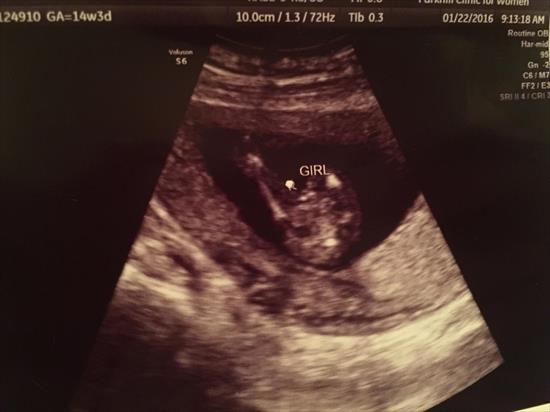

Of course at 14w 3d they can't give 100% on the gender, but they guessed girl. I'm not 100% convinced, so I thought I'd ask for your opinions! :)Attachment 29648Attachment 29649

Hard to tell. I don't see the tell tale 3 lines. Probably right if that's what they guessed.

I would not personally feel confident that was a girl. But I do get a girly vibe from the 2nd pic for some reason.